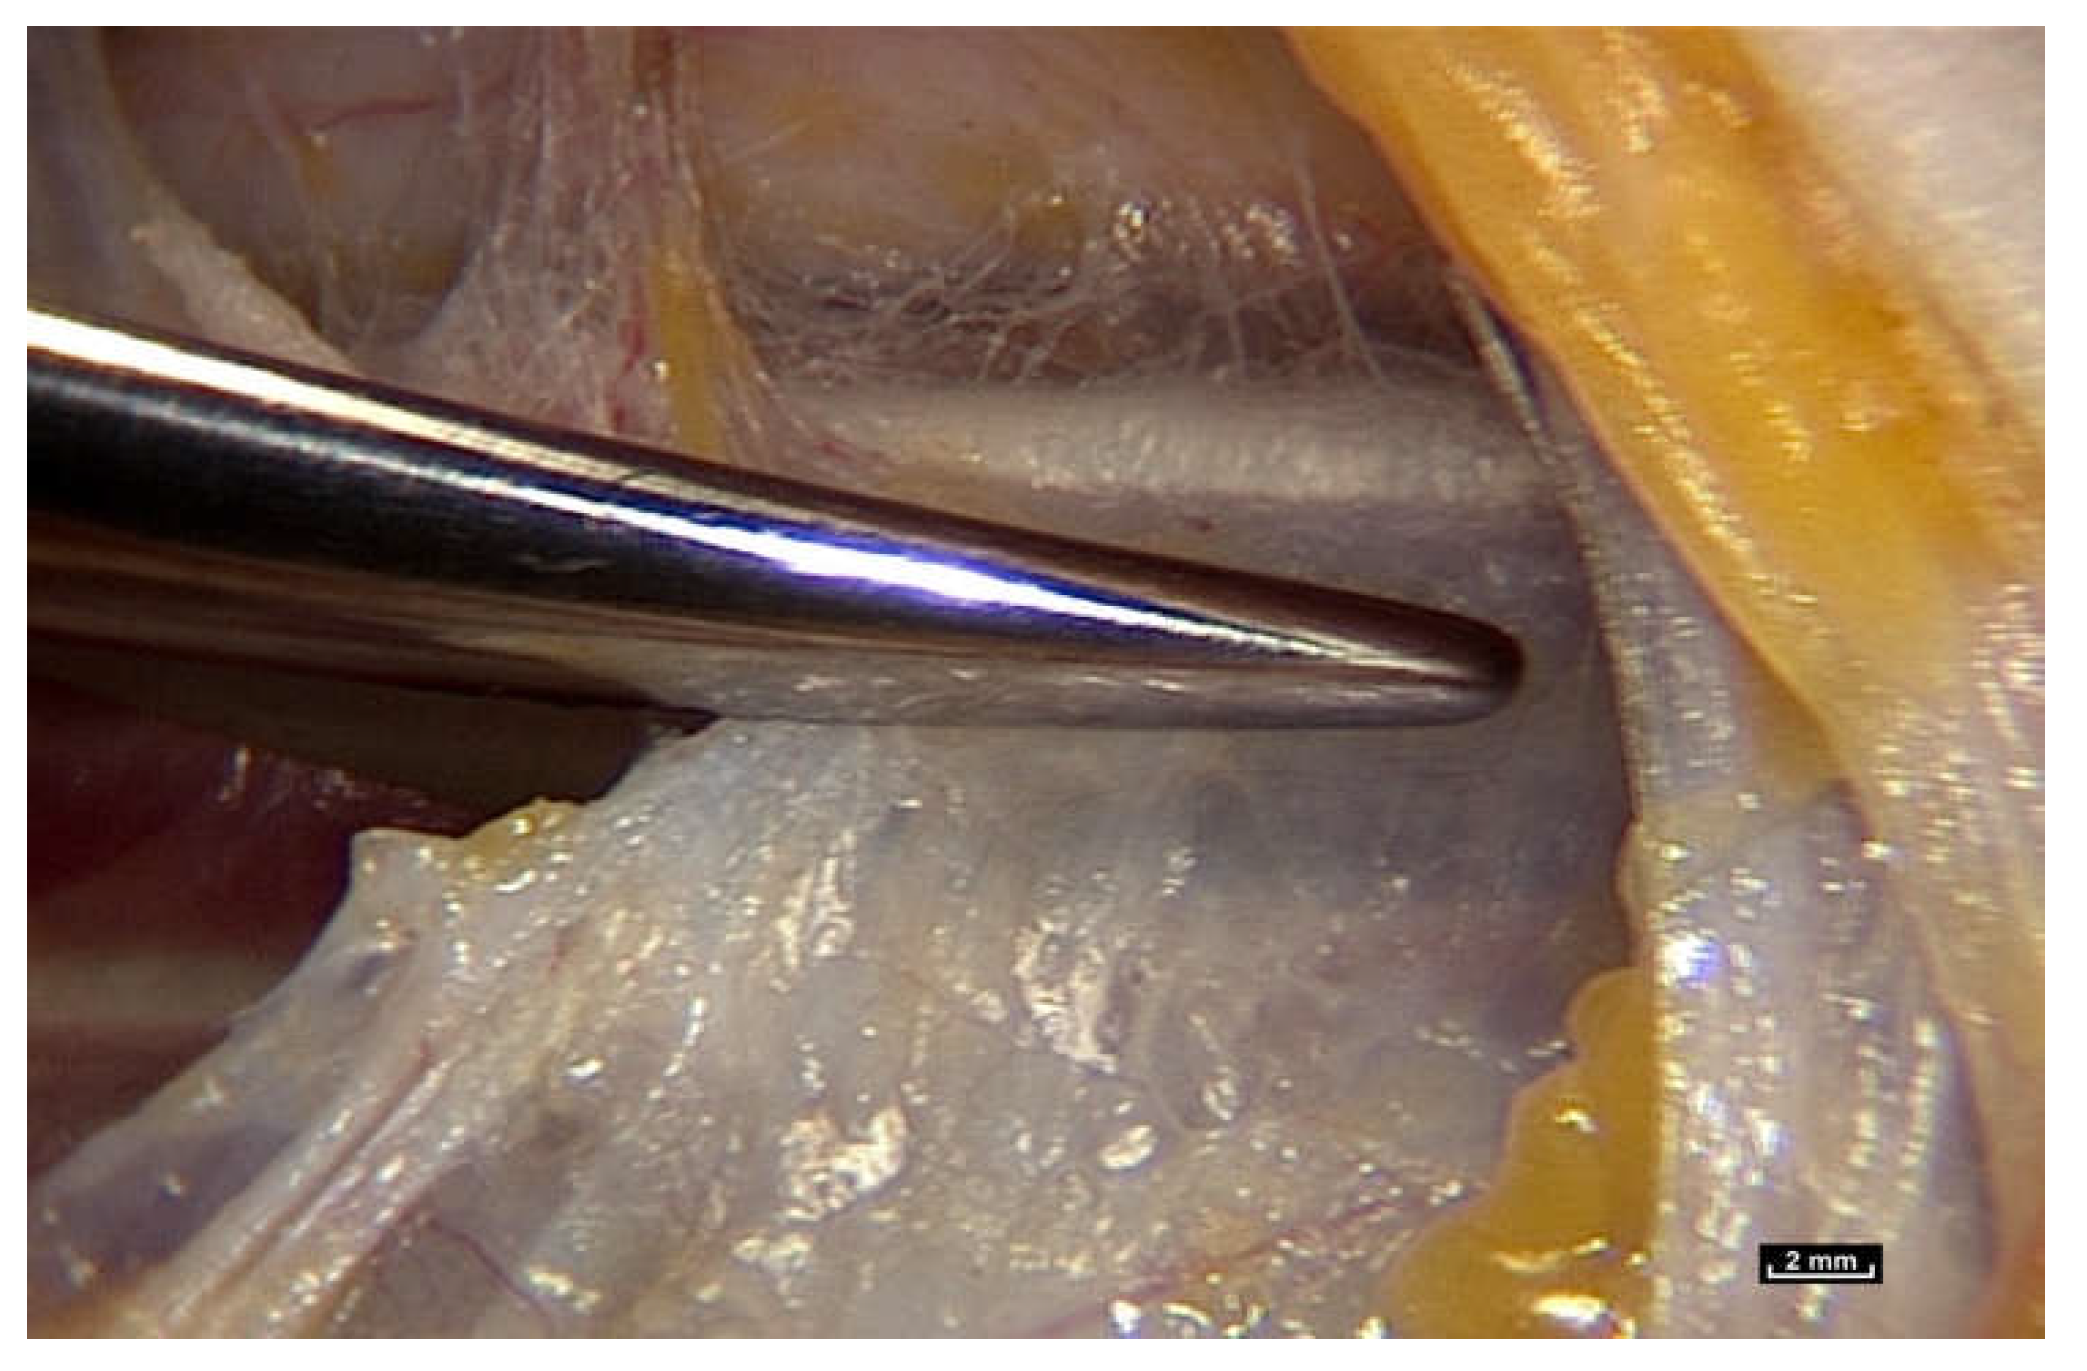

To find out, we had to review how the gliding mechanism works by using an innovative new technology, intra-tissue endoscopy. This involves placing the endoscope inside the tissues under observation during surgery. Intra-tissue endoscopy at this level of observation was made possible by the use of an endoscopic contact probe (ref. Storz, Hamou, 26120BHA Hopkins system, Karl Storz, Tuttlingen, Germany, 30° angle view, 2.9 mm diameter, 30 cm length and a magnifying capacity of 60×), connected to a high-definition processor (ref. Karl Storz “Image One” camera, Karl Storz, Tuttlingen, Germany) coupled to a cold light source (ref. Xenon Nova 201215, Karl Storz, Tuttlingen, Germany) (Figure 2).

Figure 2. (Video S2) Use of the endoscope during surgery. Viewing the video in real time on a screen in the operating theatre during surgical endoscopy.